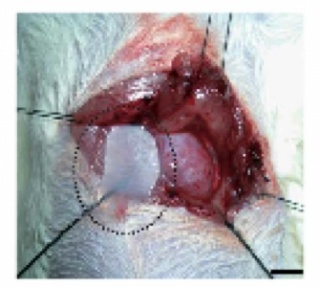

The myocardium is made up of cells called cardiomyocytes. These cells do not readily proliferate to repair surrounding tissue damages, thus rendering most untreated heart tissue damages permanent. Myocardial infarction (MI), also known as heart attack, is one of the leading causes of heart failure [3]. MI occurs when blood supply to the myocardium itself is inhibited, causing the tissue to die. With constant stress and strain being applied during each heartbeat, it is often critical to replace the weak tissue. Currently, this is most commonly done by heart transplantation. The problem with this is that the number of organ donors is not nearly enough to support the growing number of heart attack patients, especially in the United States. The use of cell sheets offers a means of providing viable cells that can patch over the damaged tissue and also proliferate. Adipose tissue-derived mesenchymal stem cells (ADMSCs) are manipulated in vitro to create cardiomyocyte-like cells (CLCs) which comprise the cell sheets [5]. These stem cells can come from the patient, creating less of a chance of rejection. The cell sheet is placed onto the site of MI and allowed to take hold on the surface without the use of sutures, as shown in Figure 2 [4].